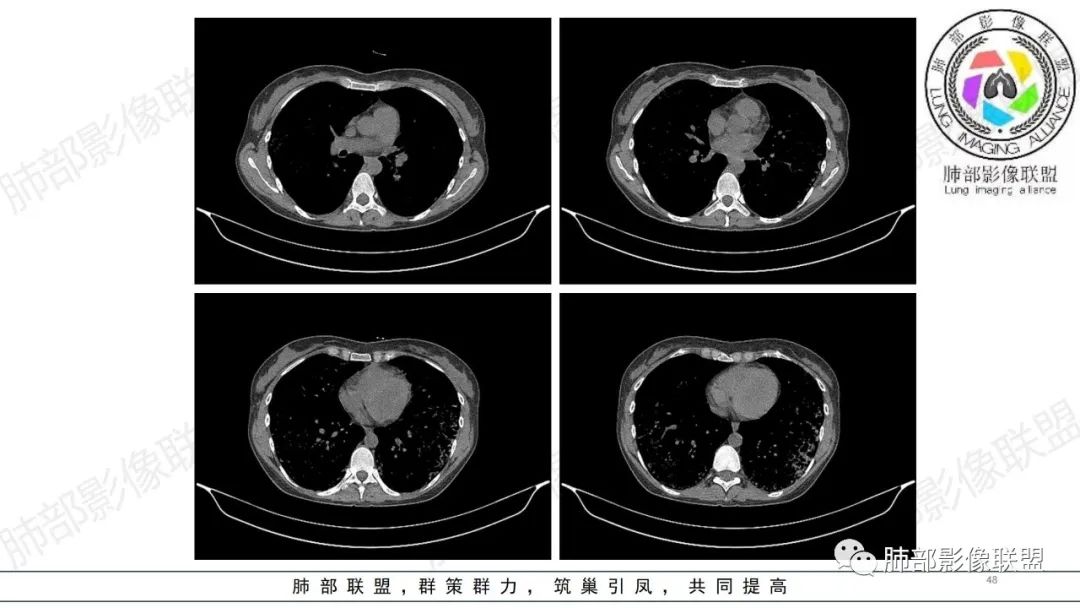

【病例】肺部弥漫大B淋巴瘤病例思考及启示

34岁女性患者,“哮喘”病史30年,近期有可疑刺激性气体吸入史;因乏力半年,咳嗽、憋气、发热4天就诊;6.1CT提示双肺广泛毛玻璃影及粟粒样结节,胸膜下闲置及血管周闲置,可见树丫征,部分小叶间隔增厚。考虑:1.过敏性肺泡炎,有可疑刺激气体接触史,胸膜下闲置,广泛毛玻璃影,地图样分布,粟粒结节边界模糊,支持过敏性肺泡炎,但糖皮激素治疗效果不佳,且动态复查血常规血红蛋白进行性降低,过敏性肺泡炎 不符合;2.肺含铁血黄素沉积症:患者30“哮喘”病史,可能为肺含铁症状,肺部CT提示双肺弥漫毛玻璃影及粟粒结节影,中下肺明显,肺底部分小叶间隔增厚,近期咳嗽、憋气、发热,血常规血红蛋白进行性下降,考虑肺含铁急性期症状,但临床无咯血症状,肺含铁不典型。综合考虑:肺含铁血黄素沉积症>过敏性肺泡炎。

年轻女性 ,急性喘息发热,肺部影像弥漫磨玻璃密度,部分细小腺泡结节,胸膜下黑线显示,短期复查,病变密度增高,下肺明显,血管周围肺组织累及较少、且逐渐成小叶间隔分布。考虑弥漫肺泡内病变,并经淋巴道转移,下肺比上肺明显,多为免疫细胞功能下肺较强。1.过敏性肺泡炎,有相关病史,三层密度特点、头尾测分布,符合。2 肺泡微石症,多有钙化,且缓慢起病,病程不太符合,放待排。3 吸入相关肺损伤,有病史,疾病演变过程也符合渗出-肉芽肿改变,建议详细询问病史。4 感染性病变,结核?病变气道分布为主,如此弥漫且没有树丫不符合。5.巨细胞病毒,可以磨玻璃 结节 改变,没有免疫缺陷病史。最后考虑吸入所致 1过敏性肺泡炎、吸入性肺损伤 鉴别肺泡微石症。

肺内气腔磨玻璃结节,肝脾肿大,治疗后间质改变,弥漫大B可能